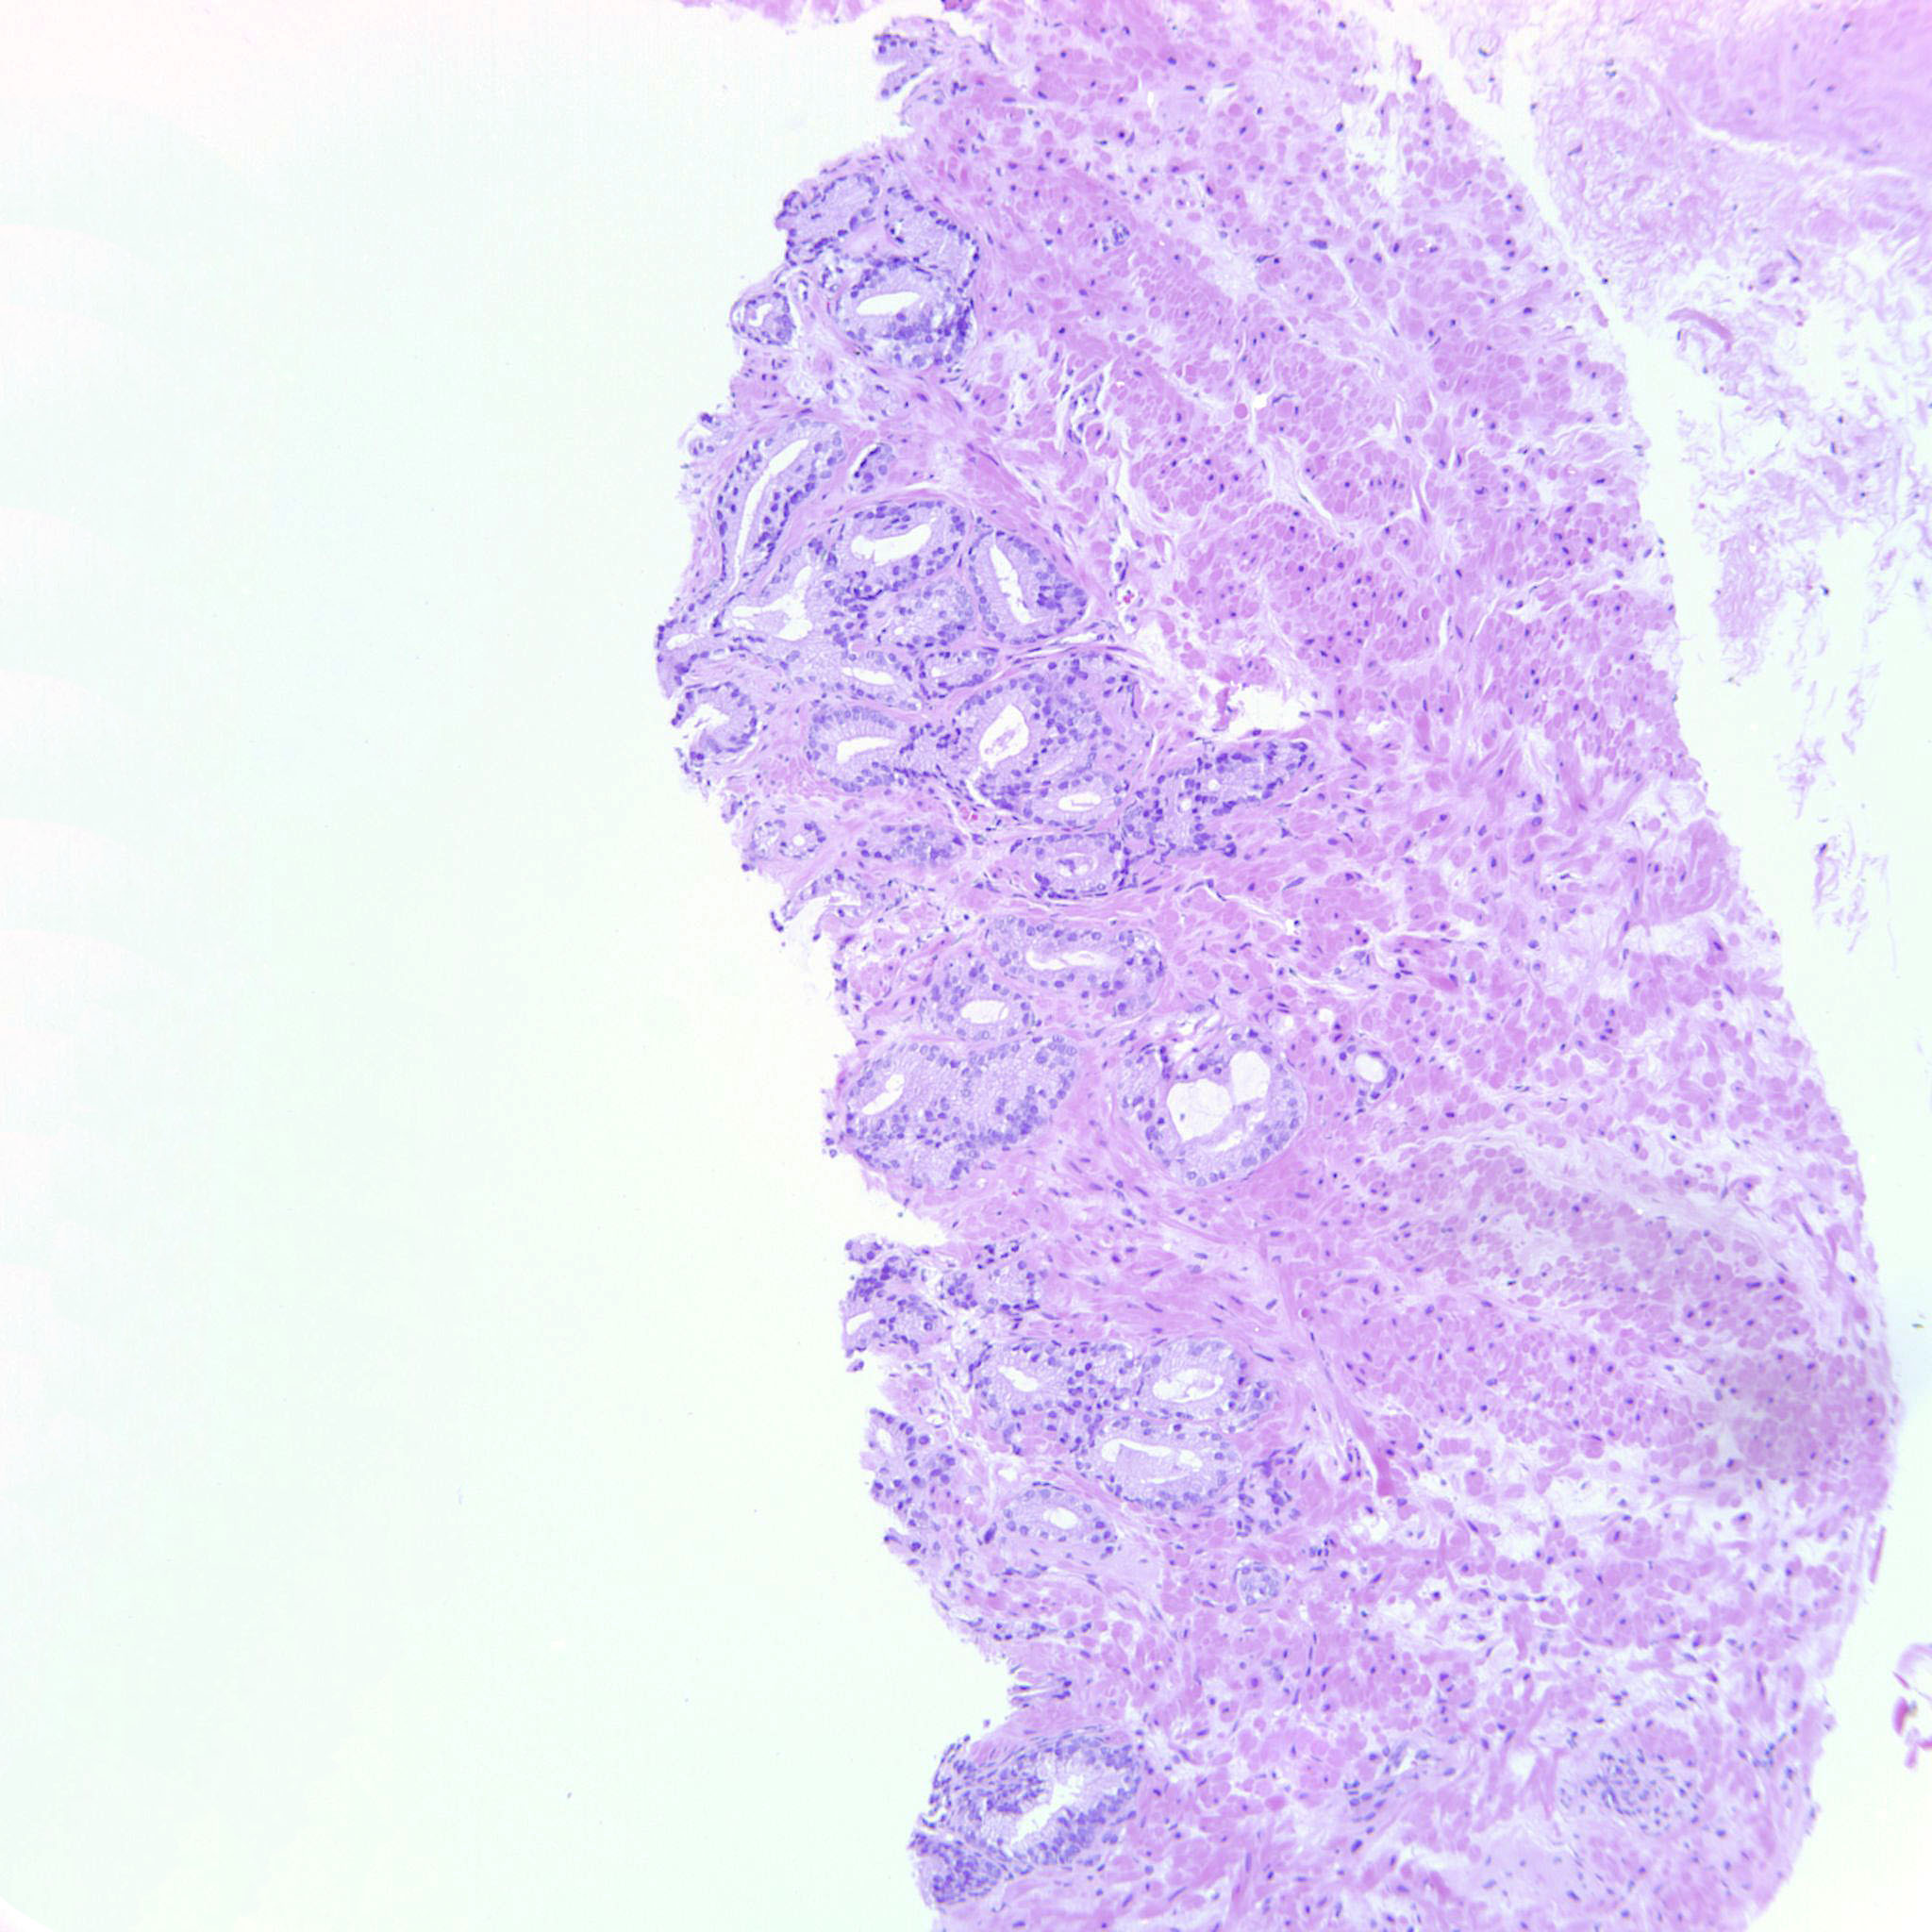

Prostate cancer grading

Case ID: 704